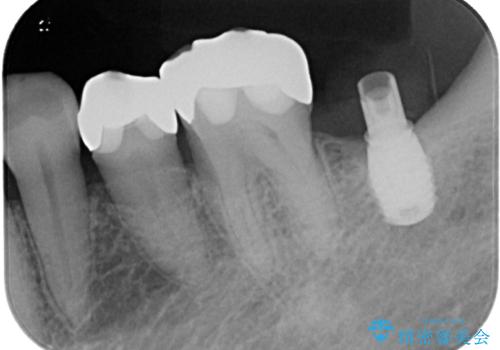

左下はインプラントによる補綴治療を行いました。

- 左下奥歯のインプラント治療と左上の被せもののやり替えを希望されて来院された患者様です。